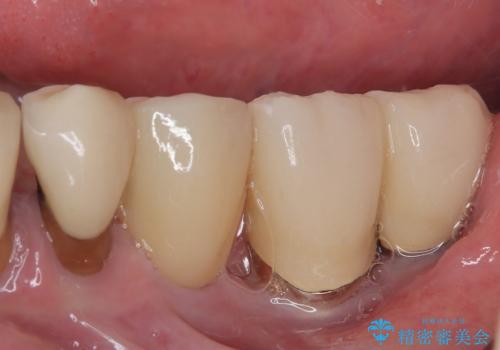

強い咬合力で歯が割れる 奥歯を1DAYインプラントで短期間治療

- 奥歯が割れてしまい、抜歯が必要となった患者様です。

以前にも歯が割れてインプラント治療を行いましたが、抜歯してからインプラント埋入→仮歯装着までに半年以上を要し、その間に残された歯への負担が大きくなり、左右反対側のセラミッククラウンが破折したことがありました。

そのため、当院に新しく導入した手法により、抜歯をした日にインプラントを埋入し、そのままを仮歯を装着することで、他の歯への負担を軽減する計画を立てました。

インプラント埋入時に植立具合の安定性を測定したところ、十分な数値が得られたため、速やかに仮歯を装着して咬合回復をさせることができました。

抜歯を含めた外科処置を1回に抑えることができ、あっという間に治療を終えることができました。